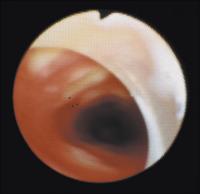

Trachea - Stenose - Lasertherapie

Abbildung 8: Status direkt nach Laserabtragung der in Abb. 7 gezeigten Stenose.

Keywords: BronchoskopieKardiologieLasertherapieStenoseTrachea